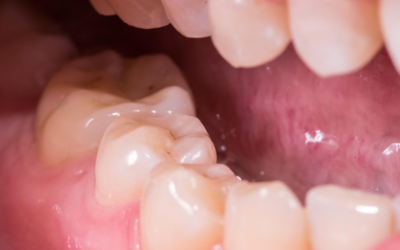

Les composites dentaires sont l’une des alternatives les plus populaires aux amalgames métalliques. Ces matériaux, fabriqués à partir de résines synthétiques et de particules de céramique, sont non seulement esthétiques, mais aussi biocompatibles. Les composites peuvent être utilisés pour restaurer les dents cariées, réparer les fissures ou recouvrir les dents décolorées, tout en préservant l’intégrité de la santé globale du patient. De plus, ils sont durables et offrent une excellente résistance à l’usure.

La céramique est un matériau largement utilisé dans la dentisterie holistique pour ses propriétés biocompatibles et esthétiques. Les couronnes et les facettes en céramique sont souvent préférées, car elles imitent parfaitement l’apparence naturelle des dents, tout en offrant une résistance et une longévité exceptionnelles. Les matériaux en céramique, comme le zirconium, sont particulièrement recherchés pour leur biocompatibilité, car ils ne libèrent aucune substance toxique dans l’organisme.